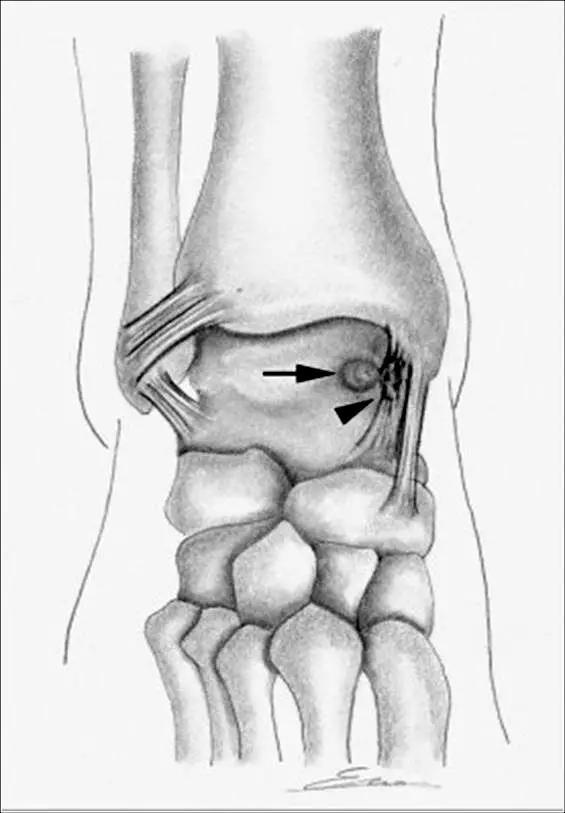

5.后内侧撞击综合症:

影像学表现为距骨胫骨间肌腱及趾长屈肌腱水肿、增厚,内踝及距骨后内侧骨赘形成。

轴位示意图示后内侧撞击综合征:M:内踝;L:外踝;TP:胫后肌腱;FDL:趾长屈肌腱;Talus:距骨。短箭:距骨胫骨间肌腱深层纤维;箭头:距骨胫骨间肌腱后部纤维。